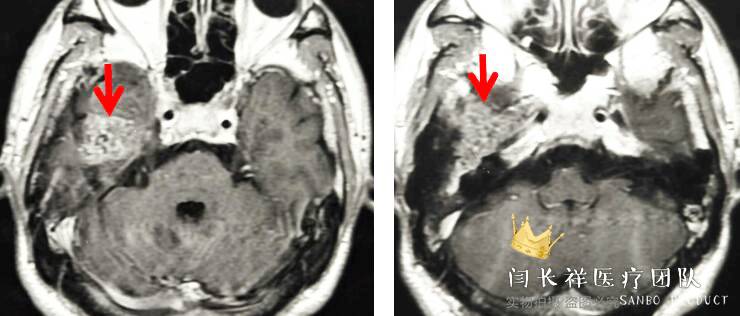

术前MRI轴位T1扫描示病灶呈等信号。

中颅窝-颞下窝占位

术前MRI轴位T2扫描示病灶侵及面神经膝段及中耳骨质。

术前MRI轴位T1增强示病灶显著不均匀强化。

术前MRI矢状位T1增强。

术前MRI冠位T1增强示病灶主体位于硬膜外,侵蚀中颅窝底骨质并朝颞下窝、翼腭窝生长。